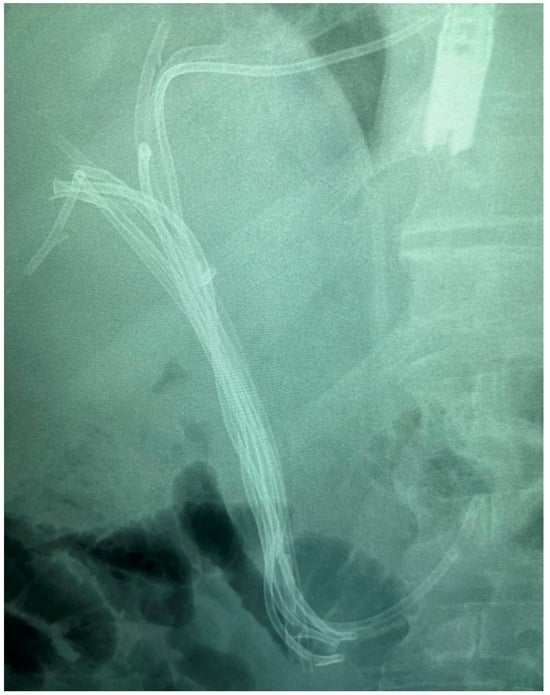

6.4.2. Endoscopic Retrograde Cholangiopancreatography (ERCP)

7.1.2. Endoscopic Nasobiliary Drainage (ENDB)